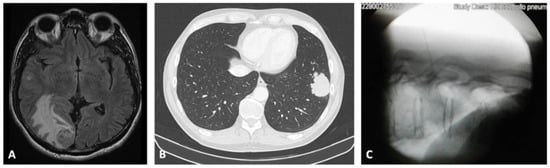

3.1. Case 1

3.2. Case 2

3.3. Case 3

3.4. Case 4